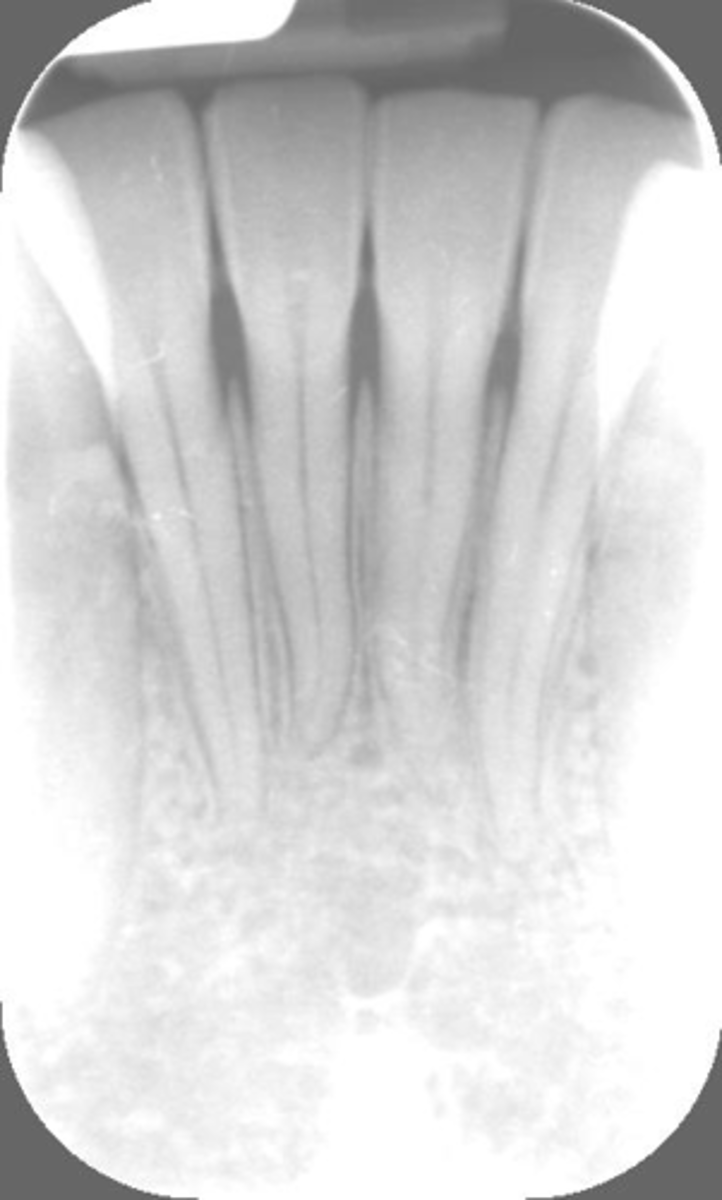

Rinn instrument bar, vertical angulation

What is this error?